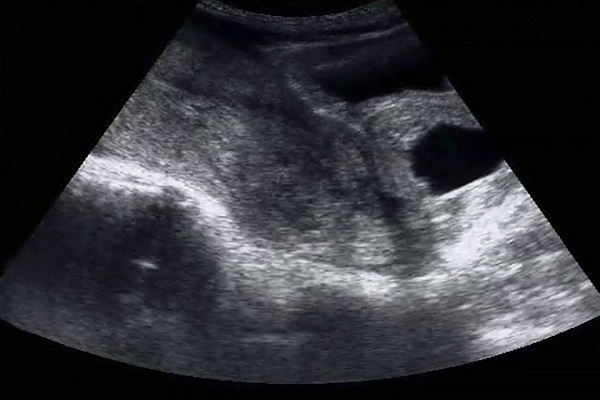

In a truly heart-wrenching post, Emily recalled finding out that she had miscarried, during her first ultrasound.

Instinctively, she knew that something was wrong, because she wasn’t seeing what she usually saw in her girlfriends’ ultrasound posts.

“I saw nothing because my body was just hours away from miscarrying,” she wrote.